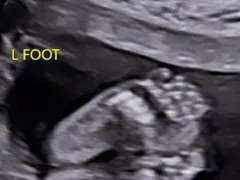

Jessie J și-a surprins fanii cu imagini de colecție din timpul saricinii mult dorite. Cântăreața nu a mai ținut ascuns marele secret și a publicat o serie de imagini emoționante cu burtica de gravidă.

„Ieri dimineață râdeam cu o prietenă care spunea «serios, dar cum voi trece peste concertul meu în LA mâine seară fără să spun întregului public că sunt însărcinată». Până ieri după-amiază îmi era teamă să trec peste concert fără să stric ceva. După ce am făcut a treia ecografie, medicii mi-au spus că inima bebelușului s-a oprit.